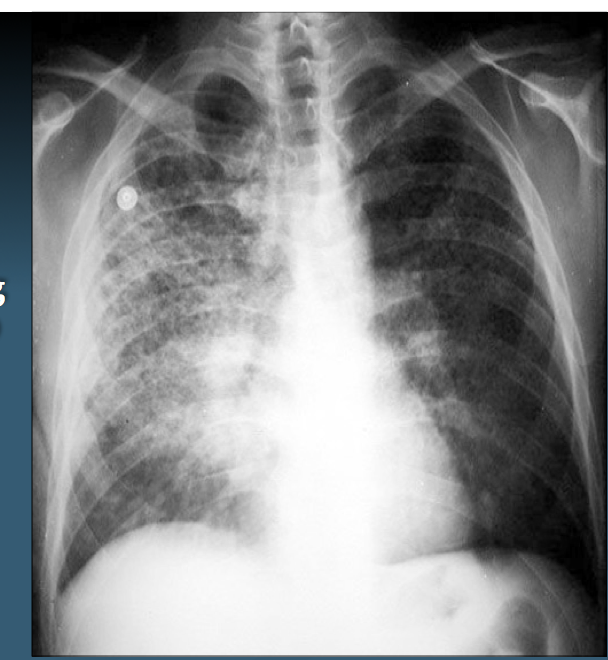

The following are hallmarks of which dz?

Hypoxemia & bilateral radiographic opacities

Acute Respiratory Distress syndrome (ARDS)

(note- this is NOT the same as respiratory distress syndrome in newborns)